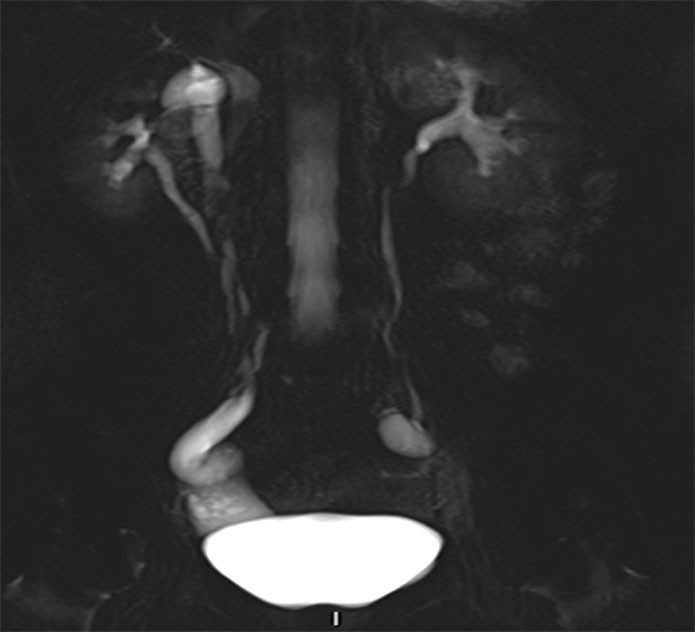

CT av urinveier ble utført, men det var ikke mulig å gi noen konklusjon med hensyn til ektopisk munnende ureter. Det ble derfor utført MR av urinveiene. Det forelå dobbeltanlegg på høyre side med et lite øvre anlegg og et dilatert ureter (fig 1). Ureter forløp dilatert mellom urinblære og vagina og munnet ut ektopisk nær urethras utmunning (fig 2).

For å identifisere dobbeltanlegg og ektopisk munnende ureter på CT forutsettes tilstrekkelig funksjon og kontrastutskilling fra det øvre anlegget, noe som ikke var tilfellet for denne pasienten. Ultralyd kan identifisere dilatert, ektopisk ureter, men det kan være vanskelig og krever som regel spesiell oppmerksomhet. Vår pasient var henvist med spørsmål om kolelitiasis og pyelonefritt, og det ble ved rutinemessig vurdering av urinveiene ikke oppdaget patologi. Høyoppløselige væskesensitive MR-sekvenser i volumopptak gir gode forutsetninger for å identifisere ureter og følge ureters forløp. I det lille bekken er MR bedre egnet enn CT, men mer tidkrevende. Det ble utført dedikerte høyoppløselighetsserier i bekkenet supplert med mindre detaljrike sekvenser over øvre urinveier. Det ble ikke benyttet kontrastmiddel under MR-undersøkelsen. Barnelegene bruker MR som primær modalitet ved mistanke om ureteral ektopi.